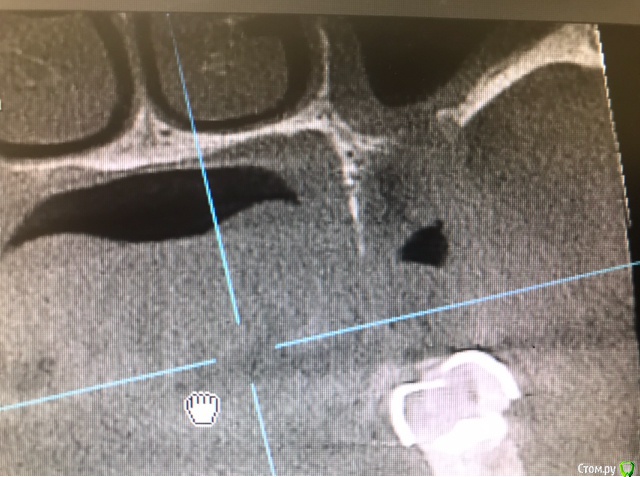

Bier Опубликовано 15 марта, 2019 Поделиться Опубликовано 15 марта, 2019 а на каком уровне срез? Ссылка на комментарий

колесников Опубликовано 15 марта, 2019 Автор Поделиться Опубликовано 15 марта, 2019 По середине Ссылка на комментарий